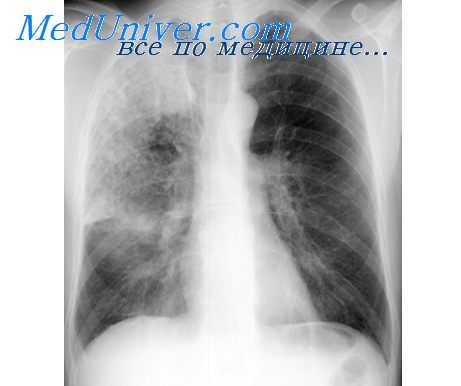

В эксперименте показано, что контакт с аллергеном сенсибилизированных мышц дыхательных путей приводит к увеличению поступления в них натрия. При исследовании концентраций одновалентных катионов у больных БА было установлено повышение в эритроцитах уровня Na+. По мнению авторов, обнаруженный прирост натрия через активацию Na/Ca обмена может приводить к накоплению Са+2 в клетке, что подтверждает кальциевую гипотезу астмы.

Механизмы увеличения концентрации натрия в клетках изучены пока недостаточно. Активность Na-K АТФазы и Na+/K+/2Cl-котранспорта в лимфоцитах и эритроцитах у больных астмой и хронической обструктивной болезнью легких не отличалась от нормальной. Недавно в крови больных БА был обнаружен сывороточный фактор, повышающий транспорт натрия в лейкоциты. Скорость поступления Na в клетки коррелировала с величиной гиперреактивности бронхов к метахолину.

У больных хронической обструктивной болезнью легких, осложненной дыхательной недостаточностью и легочным сердцем, обнаружена задержка выделения с мочой натрия и жидкости после введения нагрузочных доз поваренной соли и воды. Обнаруженные нарушения авторы связывают с повышением концентрации в сыворотке крови альдостерона и вазопрессина, а также снижением почечного кровотока и клубочковой фильтрации.

Примером заболевания, при котором биохимический дефект обусловлен генетически детерминированным нарушением транспорта ионов в эпителии дыхательных путей, является муковисцидоз. Считается, что эта болезнь обусловлена мутацией гена, ответственного за синтез специфического белка (transmembrane regulator, CFTR). Последний регулирует движение Сl- и Na+ через апикальную мембрану эпителиальных клеток.

При снижении синтеза CFTR уменьшается секреция хлора, повышается абсорбция натрия и воды, в результате чего увеличивается вязкость трахеобронхиального секрета и нарушается его клиренс. Это, в свою очередь, способствует развитию инфекционного воспаления дыхательных путей.

Существенную роль в регуляции бронхиальной проходимости, повидимому, играют К+ каналы. Через последние осуществляется выход калия из клеток, приводящий к гиперполяризации их мембран. К+ каналы обнаружены в гладкомышечных и секреторных клетках, окончаниях блуждающего нерва и эфферентных волокон, а также в эпителии дыхательных путей. Они найдены в Т-лимфоцитах, базофилах и макрофагах, участвующих в развитии воспаления при астме. Описано более 10 разновидностей калиевых каналов, из которых 4 типа (потенциалзависимые, агонистзависимые, Са-активируемые и АТФ-чувствительные) представлены в бронхах.

Наибольшее значение, по-видимому, имеют Са-активируемые каналы большой проводимости, обнаруженные в дыхательных путях в значительном количестве. Установлено, что стимуляция выхода К+ из клетки через них является одним из механизмов бронходилятирующего действия агонистов и метилксантинов. Это обусловлено фосфорилированием каналов цАМФ-зависимой протеинкиназой. Кроме того, адренорецепторы непосредственно активируют их через G-протеин.

В настоящее время известны специфические активаторы АТФ-чувствительных и Са-зависимых калиевых каналов (кромокалим, никорандил, пинацидил). В экспериментальных и клинических исследованиях установлено, что они оказывают бронхорасширяющее действие и эффективны для предупреждения приступов ночной астмы. Вероятно, это обусловлено их непосредственным влиянием на гладкие мышцы бронхов, а также способностью уменьшать секрецию АЦХ и нейропептидов. Не исключено, что данные препараты обладают и противовоспалительным действием.

Таким образом, активаторы калиевых каналов представляют собой новый класс противоастматических соединений, терапевтические возможности которых нуждаются в дальнейшем изучении.

В рамках обсуждаемой проблемы особого внимания заслуживают данные о влиянии факторов питания на особенности течения БА. Впервые связь между тяжестью симптомов астмы и потреблением поваренной соли отметили A.V. Stoesser и М.М. Cock в 1938 году. В последующем у больных БА была обнаружена положительная связь между суточной экскрецией натрия и калия с мочой, с одной стороны, и величиной бронхиальной гиперреактивности бронхов к гистамину и метахолину, с другой. Пищевые добавки поваренной соли приводили к увеличению частоты обострений астмы, ухудшению бронхиальной проходимости, повышению неспецифической гиперреактивности бронхов и потребности больных в ингаляционных стероидах. В эпидемиологических исследованиях, выполненных в Великобритании, была обнаружена связь между потреблением хлорида натрия и смертностью от БА. Тем не менее, эти данные не нашли своего подтверждения в работах других авторов.

Таким образом, несмотря на противоречивость полученных данных, можно предположить, что но крайней мере часть больных БА является калий- и соль-чувствительными. Не исключено, что нарушения обмена Na и К+ имеют определенное значение в развитии воспаления дыхательных путей. Вместе с тем, этот вопрос требует дальнейшего изучения.